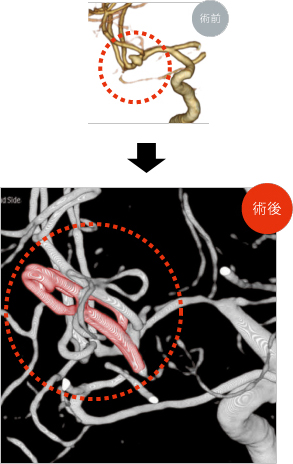

もやもや病

もやもや病とは脳の血管が通常の血管と異なり、文字通り「もやもや」とした血管に見えることから名づけられた病気です。内頚動脈という脳に栄養を送る太い血管の突き当り部分が細くなり、脳の血流が足りなくなることで症状が出現します。この血流不足を補うために太い血管から枝分かれした細い血管が拡張・新生することで通常みられないもやもや血管が出現します。この血管は脆く部位によっては出血しやすいことがわかっています。

◯外科的治療

内科的治療には限界があるため手術が必要となる場合があります。血流不足の場合は足りない血液を他の血管から補う手術を行います。多くは皮膚の血管を脳の血管とつなぎバイパスと呼ばれる別の血液が流れるルートを作ることで血流不足を改善させます。出血した場合についても、出血が落ち着いたあとに同様のバイパス手術を行います。手術により血流不足を補うことで異常に発達した弱いもやもや血管への負担を減らす効果があります。